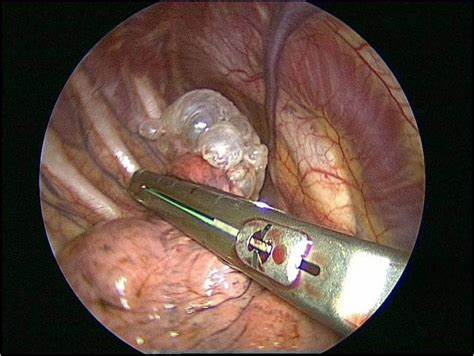

- 수술(소기포절제)